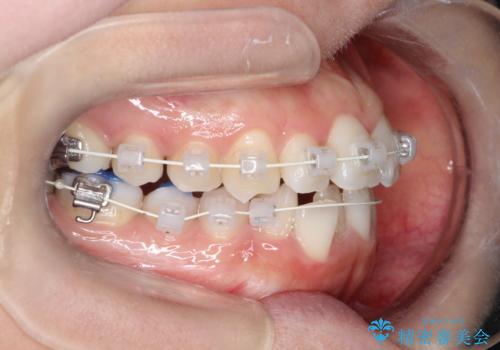

【ワイヤー矯正】前歯の凸凹を非抜歯で治療

- 前歯の凸凹を主訴に来院されました。

側方拡大にてスペースを作ることにより綺麗に前歯を並べることができました。

前歯の凸凹がある場合は治療計画を立てる上でスペースをどのように作るかが重要になります。

今回の場合は主に側方拡大でスペースの確保を行いました。